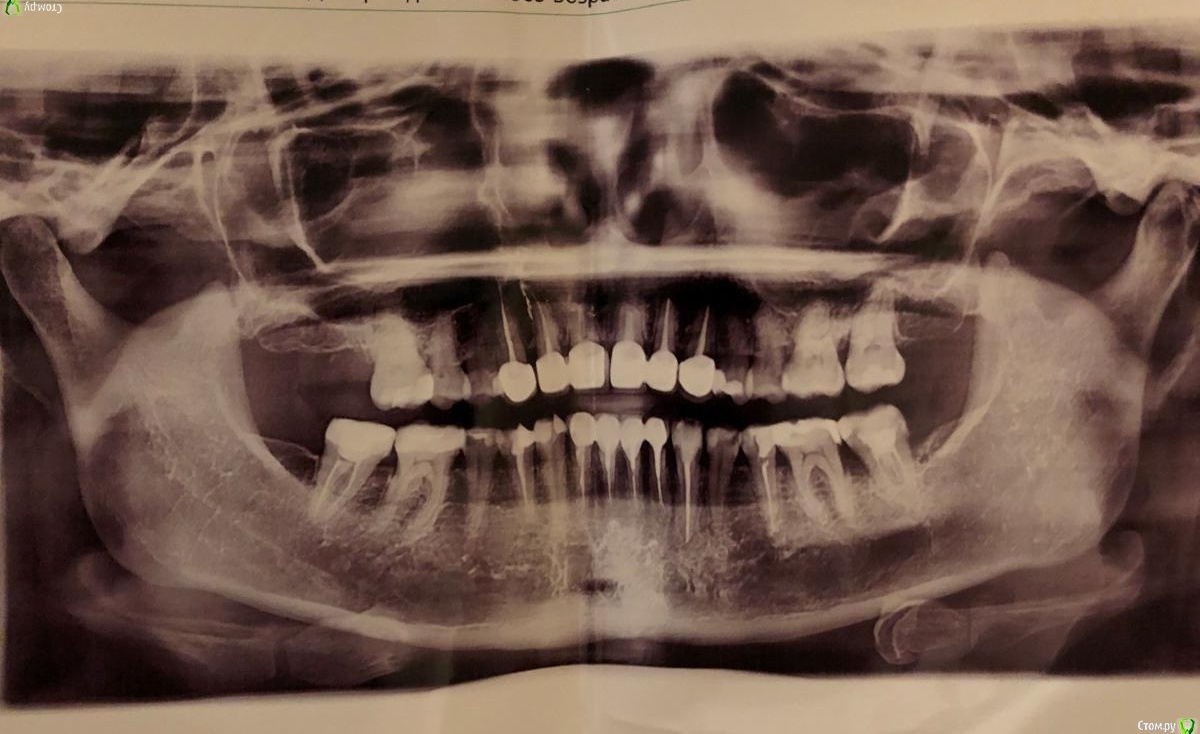

Vikalants Опубликовано 7 января, 2021 Поделиться Опубликовано 7 января, 2021 Здравствуйте, уважаемые доктора! С новым годом! Меня зовут Виктория, мне сейчас 38. У меня СОЭ 56 по состоянию на 4.01.2021. Летом 2020 - 32. С 2011 года, а может и раньше высокое соэ, 30-48. Несколько раз у меня была гранулема, один раз оперировали, второй раз пролечили. Летом 2019 года соэ 4. Уважаемые доктора, пожалуйста, посмотрите может у меня опять гранулема (прилагается панорамный снимок)? Гниет челюсть? Что делать, если это так, резекцию и заполнить костной тканью? Тогда я буду знать от чего отталкиваться и к кому идти. Почему у меня так, из-за чего, происхождение неизвестно. А может ли это быть, потому что ударилась челюстью на льду?28 лет назад я упала на льду, ударилась нижней челюстью об железку и сомкнулась челюсть, отвалились кусочки передних верхних зубов, треснули они также. Много лет болели, ныли. Местные доктора хотели их удалить, я отказалась. И только через 10 лет после падения обнаружили кисты на корнях этих зубов. Резекцию сделали. Потом через еще десять лет на соседнем зубе. И после опять. Дает ли гранулемы высокое СОЭ? Ссылка на комментарий

DmitrySH Опубликовано 9 января, 2021 Поделиться Опубликовано 9 января, 2021 По данному снимку сложно что-то конкретное сказать. Что беспокоит? Ссылка на комментарий

DmitrySH Опубликовано 9 января, 2021 Поделиться Опубликовано 9 января, 2021 post-49841-0-21351700-1610060233.jpeg Да снимок вверх ногами можно посмотреть, это не проблема. Но на нем сложно что-то конкретное разобрать Ссылка на комментарий